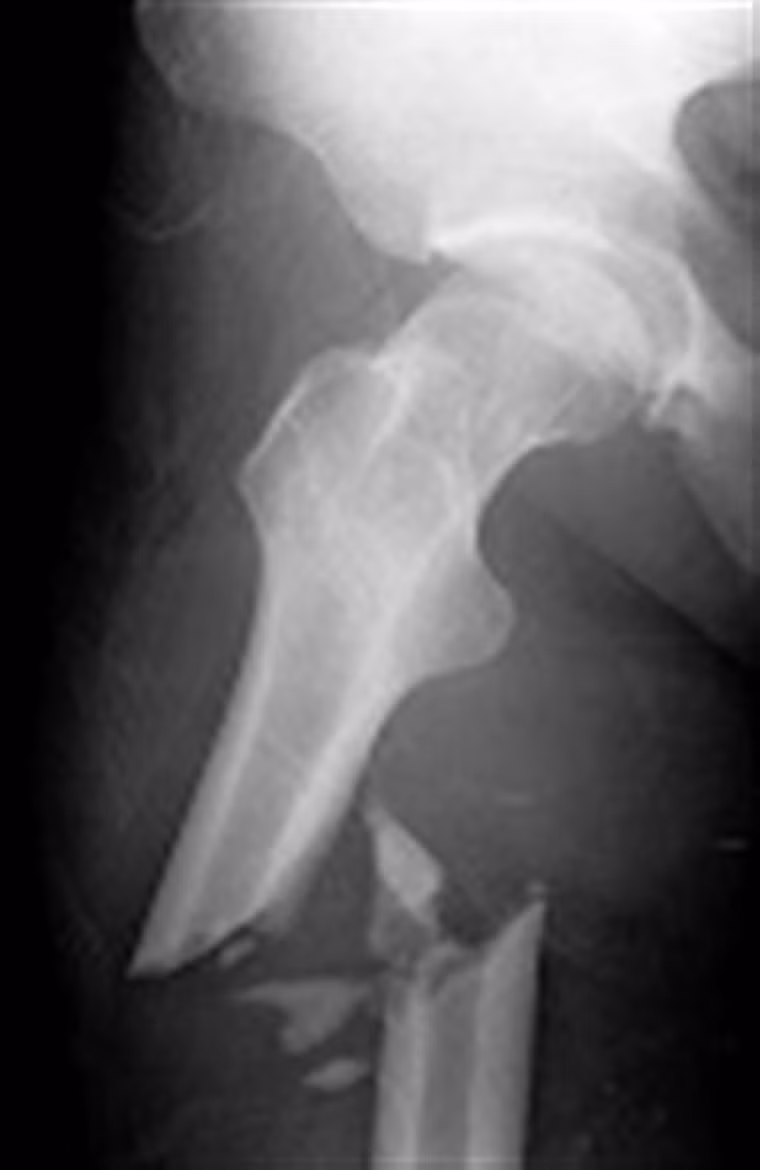

Gãy xương. Khi các tế bào ung thư phát triển trong khu vực này, nó tác động làm suy yếu xương. Ngay cả những tác động nhỏ, bất ngờ cũng khiến bệnh nhân đối diện với tình trạng gãy xương. Thậm chí, một số trường hợp khi nhập viện, các bác sĩ vẫn có thể nhầm lẫn bệnh với nguyên nhân gãy xương thông thường, tiến hành bó bột hoặc đóng đinh nội tủy.

Xuất hiện khối u. Ban đầu, khối u có thể là một đám chắc, đẩy gồ mặt da, bờ không rõ, sờ nắn không đau. Về sau to nhanh, làm biến dạng vùng có u. U thâm nhiễm tổ chức phần mềm, nổi rõ các mạch máu dưới da và tân tạo các mạch máu nhỏ, đau khi thăm khám, màu sắc da trở nên hồng, ấm hơn nơi khác, mật độ nơi mềm, nơi chắc, nơi căng do máu tụ.